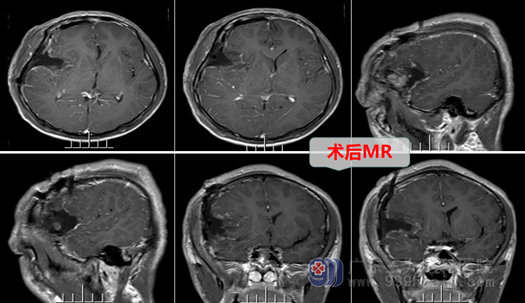

经过欧阳辉主任团队的讨论和并征得患者家属的同意后,决定做手术切除。外十科团队于11月29日在全麻下行右侧额部脑膜瘤切除术+硬脑膜修补+颅骨成形术。手术非常成功,肿瘤被完整摘除。

术后,患者神志清醒,各项功能反应正常,经过一周多时间的恢复,小伙子就开心的出院回家了。